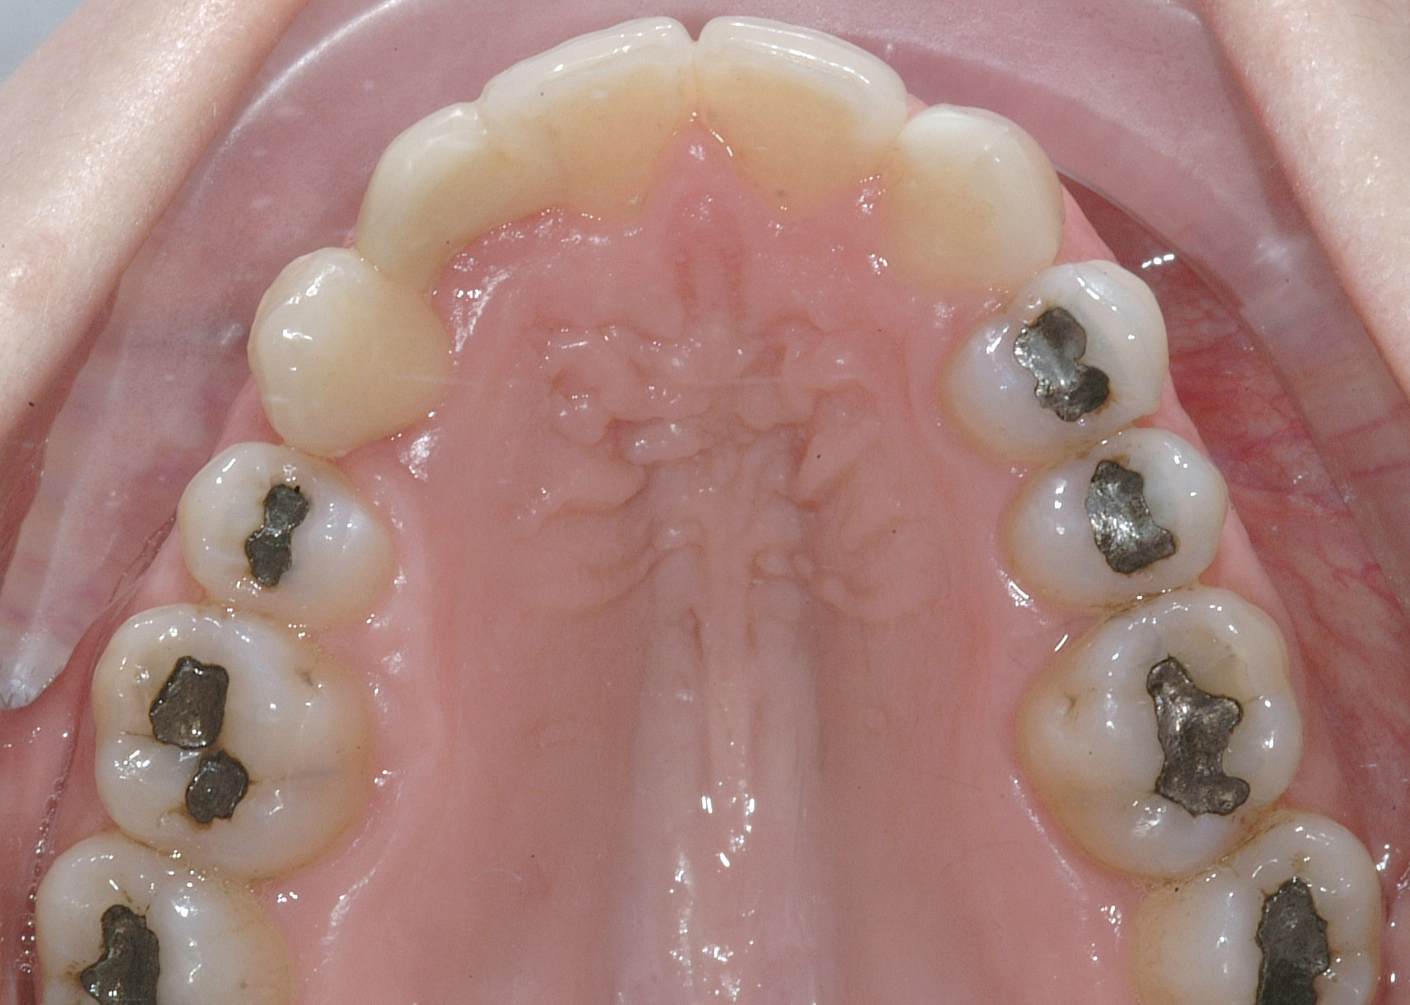

Una paziente di sesso femminile, 38 anni, già trattata ortodonticamente presso altra sede con apparecchiatura fissa a entrambe le arcate in età adolescenziale senza successiva applicazione di alcuna contenzione, si presenta alla nostra attenzione perché insoddisfatta dell’estetica del sorriso; richiede una valutazione per un trattamento ortodontico con apparecchiatura fissa linguale per la presenza di affollamento dentale a entrambe le arcate e difficoltà a mantenere una adeguata igiene orale; si riscontrano agenesia di entrambi gli incisivi laterali superiori (1.2 e 2.2) e del secondo premolare inferiore destro (4.5). Presentiamo la risoluzione del caso mediante trattamento ortodontico estrattivo a entrambe le arcate, eseguito con apparecchiatura linguale invisibile 2D e meccanica asimmetrica e seguito a medio termine da riabilitazione implanto-protesica e contenzione fissa.

Per formulare corretta diagnosi e piano di cura, lo studio del caso ha previsto la raccolta di documentazione completa standard, ovvero fotografie del viso e intraorali (Figure 1a-e), radiografia panoramica e teleradiografia del cranio in proiezione laterale (Figure 2a-b) per la relativa analisi cefalometrica e modelli di studio.

La valutazione clinica e gli esami effettuati confermano la presenza di agenesia degli incisivi laterali superiori (1.2 e 2.2) e del secondo premolare inferiore destro (4.5).

L’analisi ortodontica e la valutazione parodontale, con particolare riferimento alla posizione della radice del canino superiore destro (1.3), distoinclinata e trasposta alla radice del primo premolare (1.4) come evidente dalla radiografia panoramica e dalle immagini intraorali, ci hanno guidati nella programmazione di un trattamento estrattivo asimmetrico a entrambe le arcate.